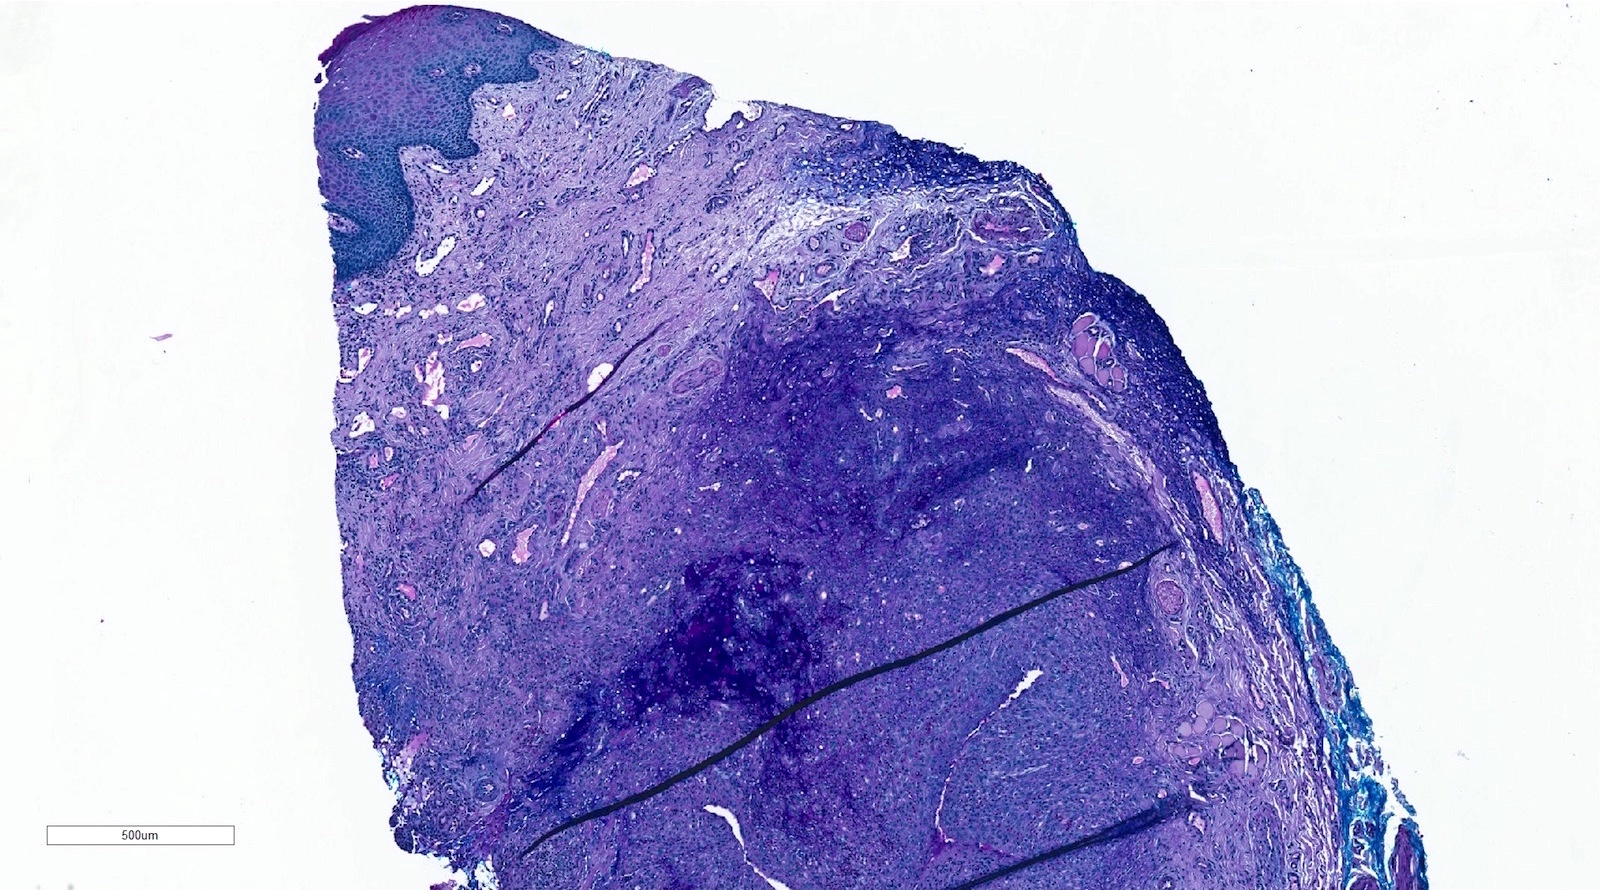

Microscopic (histologic) description

- If removed intact

- Pseudocyst cavity containing mucin, abundant epithelioid foamy histiocytes (muciphages), neutrophils and granulation tissue (Acta Histochem 2014;116:40)

- If removed ruptured

- Fragments of granulation tissue containing epithelioid foamy histiocytes (muciphages) and neutrophils, may see mucinous material (Acta Histochem 2014;116:40)

- Removed salivary gland parenchyma showing obstructive changes

- Acinar atrophy, ductal dilatation with periductal hyalinization, interstitial lymphoplasmacytic infiltrate and interstitial fibrosis at late stage (J Oral Maxillofac Surg 2008;66:2050)

- May see ruptured feeding salivary duct with squamous metaplasia (J Oral Maxillofac Surg 2008;66:2050)

- Long standing lesions organize into fibrosis resembling a fibroepithelial polyp (Acta Histochem 2014;116:40)

- No epithelial cyst lining, may see overlying surface oral mucosa with variable atrophy in superficial mucoceles (J Oral Maxillofac Surg 2011;69:1086)

Microscopic (histologic) images